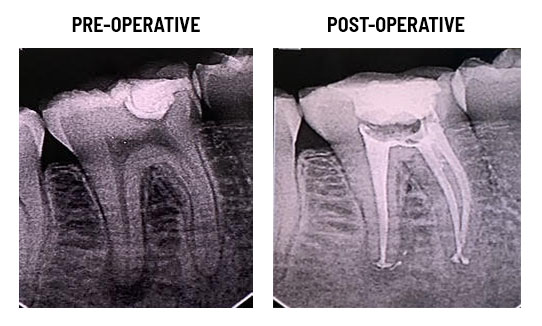

Achieving profound anaesthesia during root canal treatment is a corner stone in endodontic practice and dentistry. Profound anaesthesia during RCT benefits not only the patient, for obvious reasons, but also the dentist who will be less stressed and worrying about patient reactions and sudden movements during the treatment.